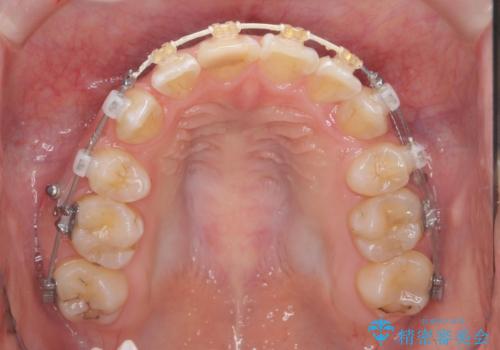

突き出た前歯を治したい 小臼歯抜歯+マルチブラケット矯正

- 矯正装置

- ワイヤー矯正

前歯の角度を改善するために小臼歯4本の抜歯を行いワイヤー マルチブラケットを用いて、しっかりと前歯の角度を改善する治療計画としました。